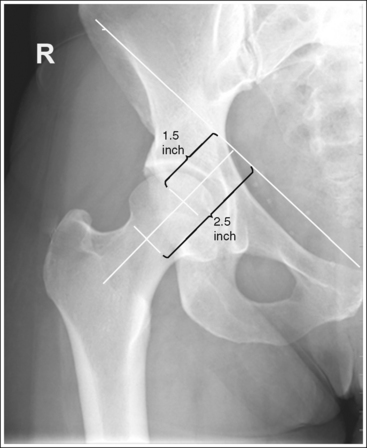

• A perpendicular central ray is centered 1.5 inches (4 cm) distal to the midpoint of a line connecting the ASIS and superior symphysis pubis, to center the hip joint in the center of the exposure field, and a perpendicular central ray is centered 2.5 inches (6.25 cm) distal to the midpoint of a line connecting the ASIS and superior symphysis pubis to place the femoral neck in the center of the exposure field (Figure 7-6). Center the IR to the central ray and open the longitudinal collimation enough to include the ASIS and any hip orthopedic apparatus. Transversely collimate to the patient's midsagittal plane and within 0.5 inch (1.25 cm) of the lateral hip skin line. Including half of the sacrum, coccyx, and symphysis pubis within the exposure field provides a way to evaluate pelvic rotation.